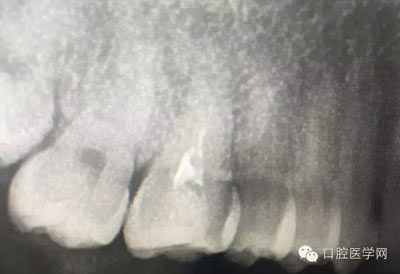

這是一例外院樹脂修復后十個月出現(xiàn)牙髓炎癥狀的患者。遇到這樣子的患者大家會怎么做,證明選擇,還有就是可做可不做治療的如何去平衡。